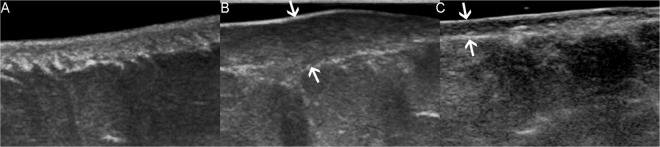

The device used to obtain B-mode images of keloids and their corresponding normal skin controls and assess skin thickness was IU22 (Philips Healthcare, Amsterdam, the Netherlands). We used the L12-5 multi-frequency linear probe operating at 5–12 MHz to acquire B-mode images in this study, whose central frequency was 7.3 MHz. In addition, the mode was superficial musculoskeletal conditions. The tip of transducer covered with several millimeters of ultrasound gel was placed smoothly to the targeted skin area along perpendicular direction and in a longitudinal section. It was of great importance to ensure that there was no pressure between the probe and skin. Figure 2 illustrates three standard B-mode images of normal skin (A), pre-treated keloid (B), and post-treated keloid accepted intralesional steriods injection (C). Skin thickness expressed in millimeter was measured from the epidermis to dermis. For the normal skin, the epidermis and dermis exhibited on the screen were depicted as high-echogenecity and medium-echogenecity, respectively. Regarding the keloid, it appeared as lower echogenic zone on the screen and sometimes was displayed as inhomogeneous area.

Figure 2.

B-mode images (in longitudinal section) of normal skin (A), pre-treated keloid (B), and post-treated keloid accepted intralesional steriods injection (C). All images were captured from the same patient. Note the evident reduction of scar thickness after treatment, which was pointed by using arrows in image B and image C. Depth and width of images A-C were 1.5 cm × 2.25 cm, 1.5 cm × 2.25 cm and 1.6 cm × 2.4 cm, respectively.